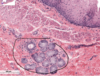

Parietal (A) & Chief Cells (B) in Stomach

Fundic gland - lumina (L) of the fundic glands can be recognized. The chief cells (CC) are granular in appearance and are much smaller than the round, plate like parietal cells (PC). Parietal cells, so their name imply, are located at the periphery of the gland. Slender connective tissue elements (CT), housing blood vessels, occupy the narrow space between the closely packed glands.